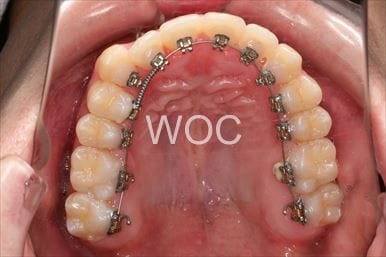

治療中1

治療中2

治療中3

治療中4

治療中5

出っ歯舌側矯正

上下舌側矯正を希望。

通院状況や歯みがきの協力が良かったため、1年7ヶ月で治療を終えることができました。※装置と注意事項に関しては、大人の矯正装置一覧へ。

- 年齢:20歳女性

- 主訴:出っ歯が気になる

- 基本矯正料金:120万円

- 治療期間:1年7ヶ月

- 抜歯部位:上顎両側第一小臼歯